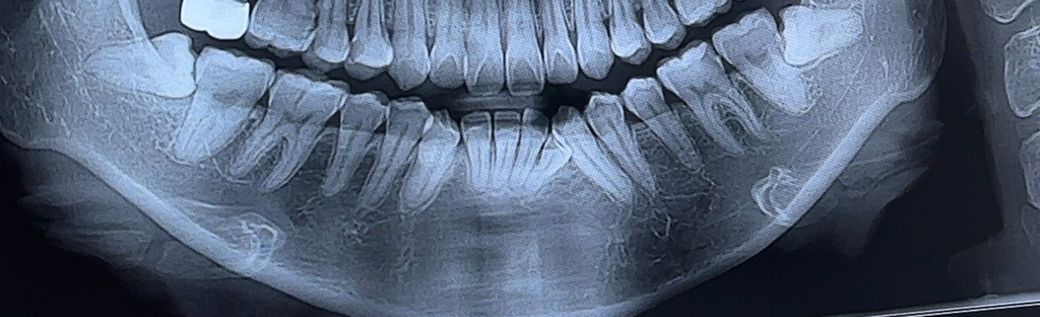

치과 원장님들 사랑니 옆에 충치 있어보이나요…?

곧 교정 하는데 궁금해서요 ㅜㅜ

사랑니 있으면 신경치료 해야겟죠 도와주세요 ㅠ

사랑니 오늘 오른쪽은 뺐어요

사랑니 옆에 충치 있어보이나요 ????

왼쪽 아래 사랑니를 발치하고 사랑니 앞의 치아를 평가해보아야 할 것 같습니다. 현재 사진으로는 두 치아가 겹쳐서 정확히 충치가 있는지 판단하기에는 어려움이 있습니다. 지금 상태에서는 발치 이후에 해당 부분을 standard view 촬영을 하는 것이 필요해보입니다. 지금으로서는 정확한 판단을 하기에는 어려움이 있습니다.